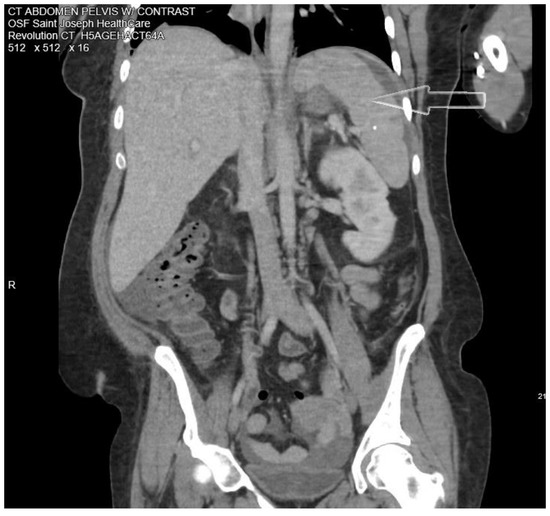

Laboratory testing showed leukocytosis with a white blood cell count (WBC) of 14 ×103/mcL with 91% neutrophils, pro-calcitonin elevated at 22.92 ng/mL, C-reactive protein (CRP) 19.37 mg/dL, erythrocyte sedimentation rate (ESR) 68 mm/h, hemoglobin A1c (HbA1c) 12.2%. She was hyponatremic, hypokalemic, and hypochloremic with values of 133 mmol/L, 3.3 mmol/L, and 96 mmol/L, respectively. A computed tomographic (CT) abdominal scan with contrast showed multiple cystic masses in the spleen with concerns of developing splenic abscess (Figure 1).

Figure 1.

Computed tomographic (CT) abdominal scan with contrast showing one of the splenic abscesses (white arrow).